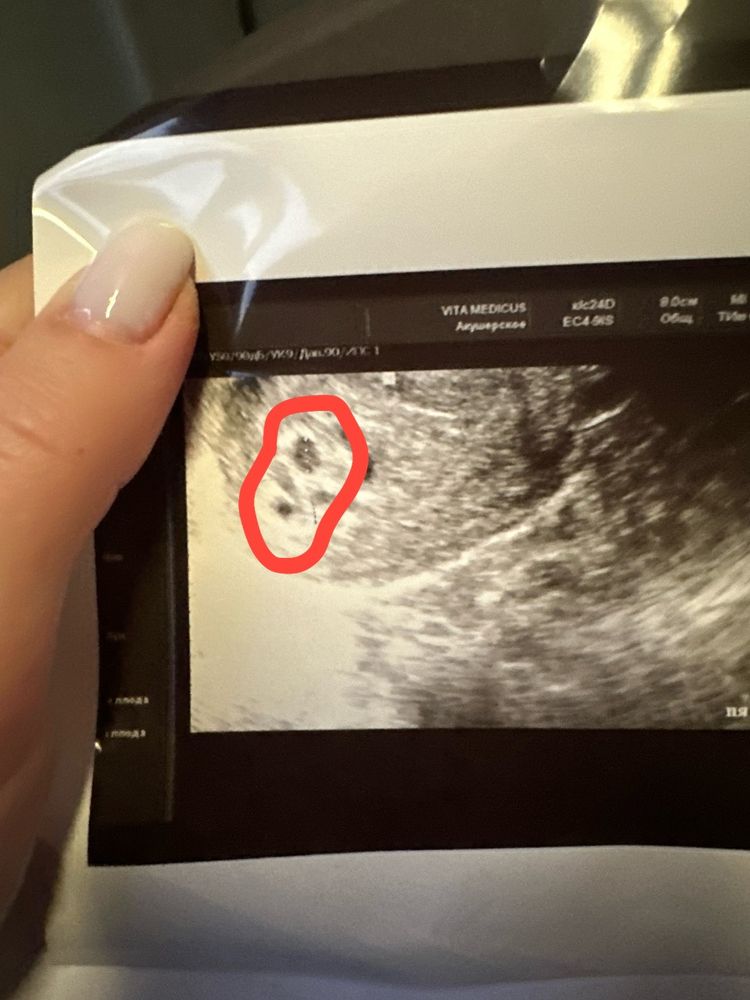

Двойня?

Не хочу вас пугать, но ни двойню не очень похоже ваше узи. Я бы помимо Хгч прямо завтра сходила к другому узисту на другой аппарат

Полина, или не развивающаяся. Или пузырный

Полина, 4 мм пя у меня было на 5 день задержки при нормальной беременности и Хгч там был 1900, а у вас уже большой Хгч и пустые пя маленьких размеров и форм

Что-то слишком маленькие плодные для срока,а уже эмбрионы такие должны быть на этом сроке

Полина, он может быть высоким как при двойне, так и при пузырном заносе, предполагаю врач ваш имел в виду именно его.. но при пузырном заносе там прям какие то космические цифры должны быть, и каждый раз на узи как-будто новое плодное яйцо появляется. картина такая обычно надо смотреть узи в динамике. но что-то для 6 недели пя маловаты.. судя по хгч овуляция точно не поздняя была

Полина, у клеарблю это максимальный срок,он при и 2000 показывает 3+ но для вашего срока такой хгч ни о чем,от уровня хгч зависит рост и размер плодного яйца,судя по размерам хгч у вас маленький и растет медленно,поэтому и пя маленькие и не соответствуют сроку,судя по динамике ниже, овуляция нормальная была,с нормальной овуляцией уже пя от 15 мм и выше и эмбрионы по 3-6 мм на таком сроке,а ваше узи как-будто овуляция 2,5 недели назад была,но у вас уже хгч положительный был

Полина, неразвивающаяся двойня,хгч сдайте в динамике